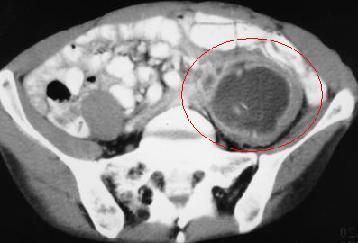

A patient presents with sudden onset of joint pain in both knees. His eyes are red and swollen, about which he says he must have picked up “pink eye” from his son. He also admits a couple week history of watery diarrhea, fever, and abdominal pain radiating to the back. CT reveals the below finding, indicated by the arrow. Diagnosis?

Yersinia enterocolitica with Reiter’s syndrome

(Mesenteric lymphadenitis shown in CT + appendicitis-like pain = Yersinia; arthritis + conjunctivitis + urethritis = Reiter’s syndrome, a complication of Salmonella, Shigella, Yersinia, and Campylobacter)